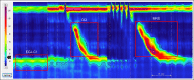

Clinical history, questionnaire data and response to antisecretory therapy are insufficient to make a conclusive diagnosis of GERD in isolation, but are of value in determining need for further investigation. Conclusive evidence for reflux on oesophageal testing include advanced grade erosive oesophagitis (LA grades C and D), long-segment Barrett's mucosa or peptic strictures on endoscopy or distal oesophageal acid exposure time (AET) >6% on ambulatory pH or pH-impedance monitoring. A normal endoscopy does not exclude GERD, but provides supportive evidence refuting GERD in conjunction with distal AET <4% and <40 reflux episodes on pH-impedance monitoring off proton pump inhibitors. Reflux-symptom association on ambulatory reflux monitoring provides supportive evidence for reflux triggered symptoms, and may predict a better treatment outcome when present. When endoscopy and pH or pH-impedance monitoring are inconclusive, adjunctive evidence from biopsy findings (histopathology scores, dilated intercellular spaces), motor evaluation (hypotensive lower oesophageal sphincter, hiatus hernia and oesophageal body hypomotility on high-resolution manometry) and novel impedance metrics (baseline impedance, postreflux swallow-induced peristaltic wave index) can add confidence for a GERD diagnosis; however, diagnosis cannot be based on these findings alone. An assessment of anatomy, motor function, reflux burden and symptomatic phenotype will therefore help direct management. Future GERD management strategies should focus on defining individual patient phenotypes based on the level of refluxate exposure, mechanism of reflux, efficacy of clearance, underlying anatomy of the oesophagogastric junction and psychometrics defining symptomatic presentations.